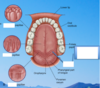

Where is the parotid duct opening?

What part of the oral cavity is this?

Upper 2nd molar.

vestibule.

What is the purpose of palatine rugae? What happens as you travel more posterior from the rugae?

help keep the food in the mouth while it is being processed.

Travel more posterior it becomes softer and more slippery which helps it slide down

What are in between the two arches here?

palatine tonsils

What are the two parts to the tongue? How big are they?

Fungiform papillae are more laterally and have taste buds.

Centrally are filiform papillae (carpet like).

Septum going down the middle.

Filiform hold the food against the teeth.